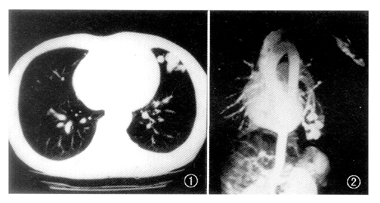

患者 男,28岁。发现左肺阴影8年。体检:精神良好,口唇紫绀,杵状指、趾明显,左胸腋前线第4~6肋间可闻及连续性Ⅱ~Ⅲ级杂音,深吸气时清晰,无传导,心前区无隆起,未触及震颤,叩诊心界不大,各瓣区未闻及杂音。实验室检查:血氧分压50.2 kPa(1kPa=7.5mmHg),氧合血红蛋白0.9,血总二氧化碳8.8 mmol/L。胸部正侧位片示左肺上舌段自肺门斜向前下有2条粗大条索状影,远段呈卵圆形膨大融合,边缘清晰锐利,拟诊:左肺动静脉血管畸形。CT平扫示左肺舌叶多个结节状密度增高影,并融合成团,边缘清晰锐利,左肺门区2条粗大血管伸入病灶,增强扫描与血管同步增强(图1)。MRI检查用GE 1.5 T机,采用心电门控触发的二维快速梯度回波成像序列,参数TR 15毫秒,TE7毫秒,层厚5 mm,层距0 mm,矩阵256×256,1次信号采集。在左肺上叶舌段近胸壁处,可见3 cm×3 cm×2 cm大小血管团影,动态增强扫描显示左上肺动脉舌段分支明显增粗,供应该异常血管团,增粗的引流静脉回流入左上肺静脉(图2)。手术所见:左上叶舌段可见3 cm×4 cm×3 cm大小血管瘤样改变,壁菲薄,搏动明显,试行阻断舌支肺动脉及左上肺静脉舌段分支,病变区搏动消失。病理检查:肺组织血管不规则扩张、扭曲,畸形明显,管壁厚薄显著不一,符合动静脉瘘。

说明:肺动静脉瘘是肺部少见病,大多为先天性,少数为胸部创伤所致。肺动脉造影是诊断本病的重要方法,可动态观察供应动脉和引流静脉走行方向和形态,但它是一种损伤性检查。MRI是一种无损伤的检查方法,它可以任意切面成像,能清楚显示病变范围、血管起始关系、形态、边界、内部结构及其与周围组织结构关系。本例运用梯度回波及动态增强扫描,清晰直观地反映了供血动脉及引流静脉的走行形态和血管数目,为设计手术方案提供了可靠的依据,本例MRI表现与手术所见一致。(收稿:1998-03-05 修回:1998-07-20), 百拇医药